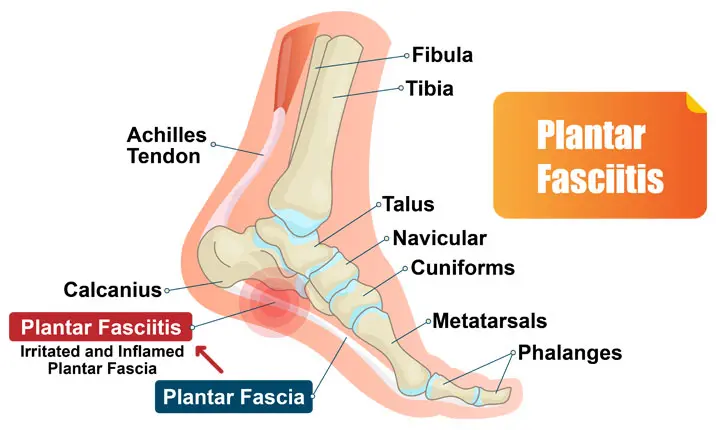

Common Conditions Causing Heel Pain

Heel Pain Causes Diagnosis Treatment

A Stabbing Heel Pain